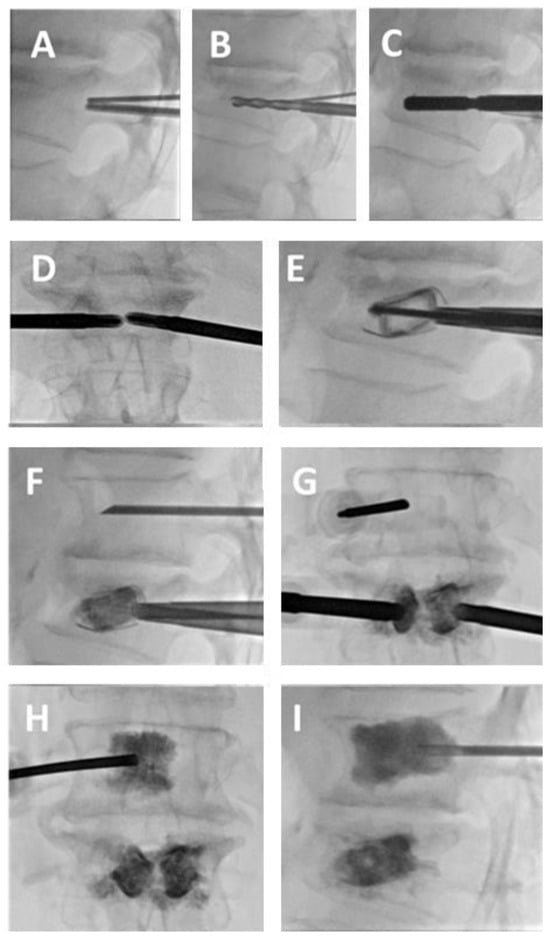

- Pusceddu, C.; Marsico, S.; Derudas, D.; Ballicu, N.; Melis, L.; Zedda, S.; de Felice, C.; Calabrese, A.; De Francesco, D.; Venturini, M.; et al. Percutaneous Vertebral Reconstruction (PVR) Technique of Pathological Compression Fractures: An Innovative Combined Treatment of Microwave Ablation, Bilateral Expandable Titanium SpineJack Implants Followed by Vertebroplasty. J. Clin. Med. 2023, 12, 4178. [Google Scholar] [CrossRef]